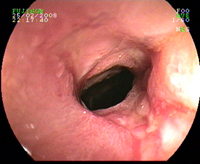

Sténose iléale. Maladie de Crohn